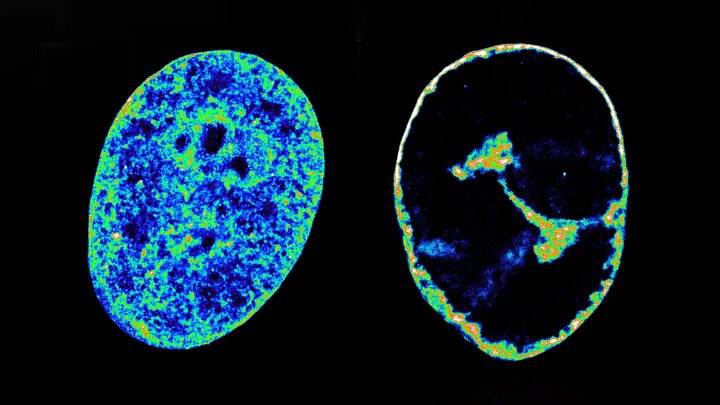

به گزارش خبرگزاری ایمنا و به نقل از ساینس دیلی، ویروس تبخال دهانی (HSV-1) که بیش از دوسوم افراد زیر ۵۰ سال به آن مبتلا هستند، نه‌تنها سلول‌های میزبان را اشغال نمی‌کند، بلکه به‌طور فعال ساختار سه‌بعدی ژنوم انسان را بازآرایی می‌کند تا به ژن‌های مورد نیاز برای تکثیر خود دسترسی پیدا کند، مطالعه‌ای جدید که در نشریه Nature Communications منتشر شده، نشان می‌دهد که HSV-1 ظرف چند ساعت پس از ورود به سلول، با استفاده از آنزیم‌های میزبان همچون تاپویزومراز I، DNA انسان را فشرده کرده و آن را به سمت لبه هسته سلول منتقل می‌کند، این بازچینی موجب آزادسازی فضای کافی برای تشکیل کارخانه‌های تولید ویروس در هسته می‌شود.

محققان با استفاده از میکروسکوپی فوق‌رزولوشن و تکنیک Hi-C توانستند تعاملات DNA را در فضای هسته سلول با دقت بی‌سابقه‌ای بررسی کنند. یافته‌ها نشان داد که مسدودسازی آنزیم تاپویزومراز I توانست به‌طور کامل مانع بازآرایی ژنوم و در نتیجه توقف تولید ویروس شود.